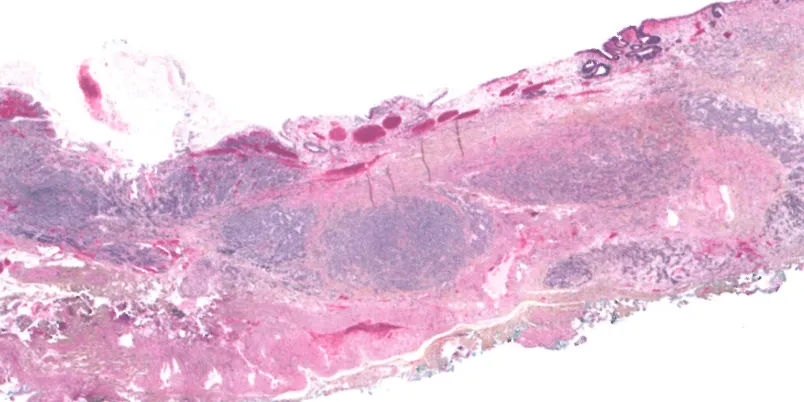

三、MiNENs:

通常由低分化神经内分泌癌(NEC)与鳞状细胞癌/腺癌组成

尚不明确,下食管黏膜下腺或Barrett食管中存在内分泌细胞。